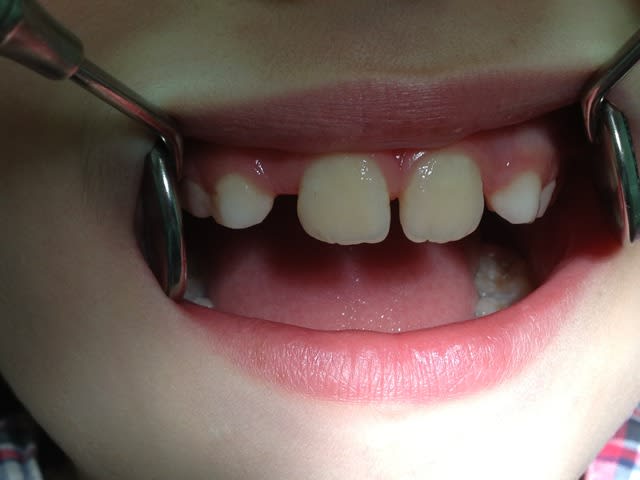

Re!!! Voilà de nouvelles photos, donc pour résumer ,enfant de 7ans auquel l'ortho me demande d'extraire les 4 canines de lait pour laisser la place aux latérales.Probléme ;est ce que l'expansion est possible:Merci de toutes vos réponses

La ddm est pas si terrible que ça!

Comment elle deglutit? Rsspiration nasale ou buccale? Bruxe? Ronfle? Sommeil agité????

En ce qui me concerne on commencerait pas expansion fonctionnelle, planas, soulet et besombes, orthoclonic, pourquoi pas quad helix si tu trouves pas mieux mais certainement pas extraire.